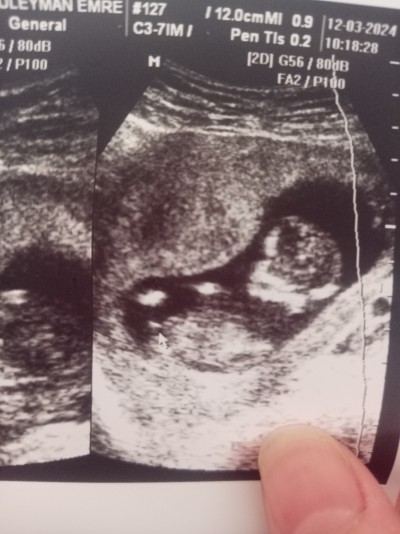

sizce cinsiyet nedir ayrıntıyı gören tecrübe eden varmi

Erkek canım resmen bebeğin pipisi gôrünüyor

Doktor erkek demedi ama bak ok işaretiyle gösteriyorum dedi sen anla dedi pipi böylemi görünüyor ultrasonda doktor şaşırmis olabilir mi

Erken diye cnm 13 haftalikti daha

Erkekmiş 21 haftalığım

Erkek benim